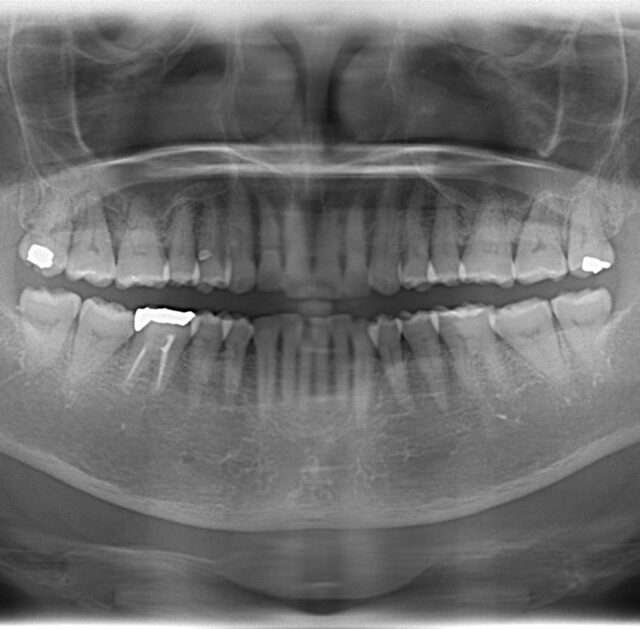

歯周病